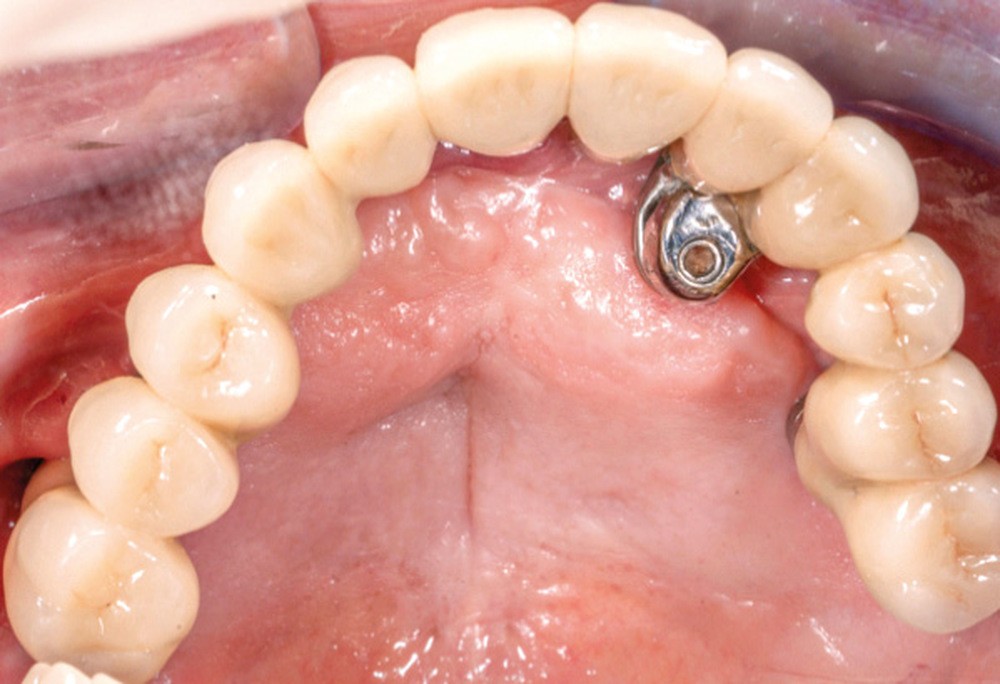

Dans le cas clinique présenté dans cet article, le patient édenté total bimaxillaire se plaint d’une gêne importante et d’une insatisfaction de son sourire en lien avec un plan d’occlusion prothétique inadapté (fig. 1 et 2).